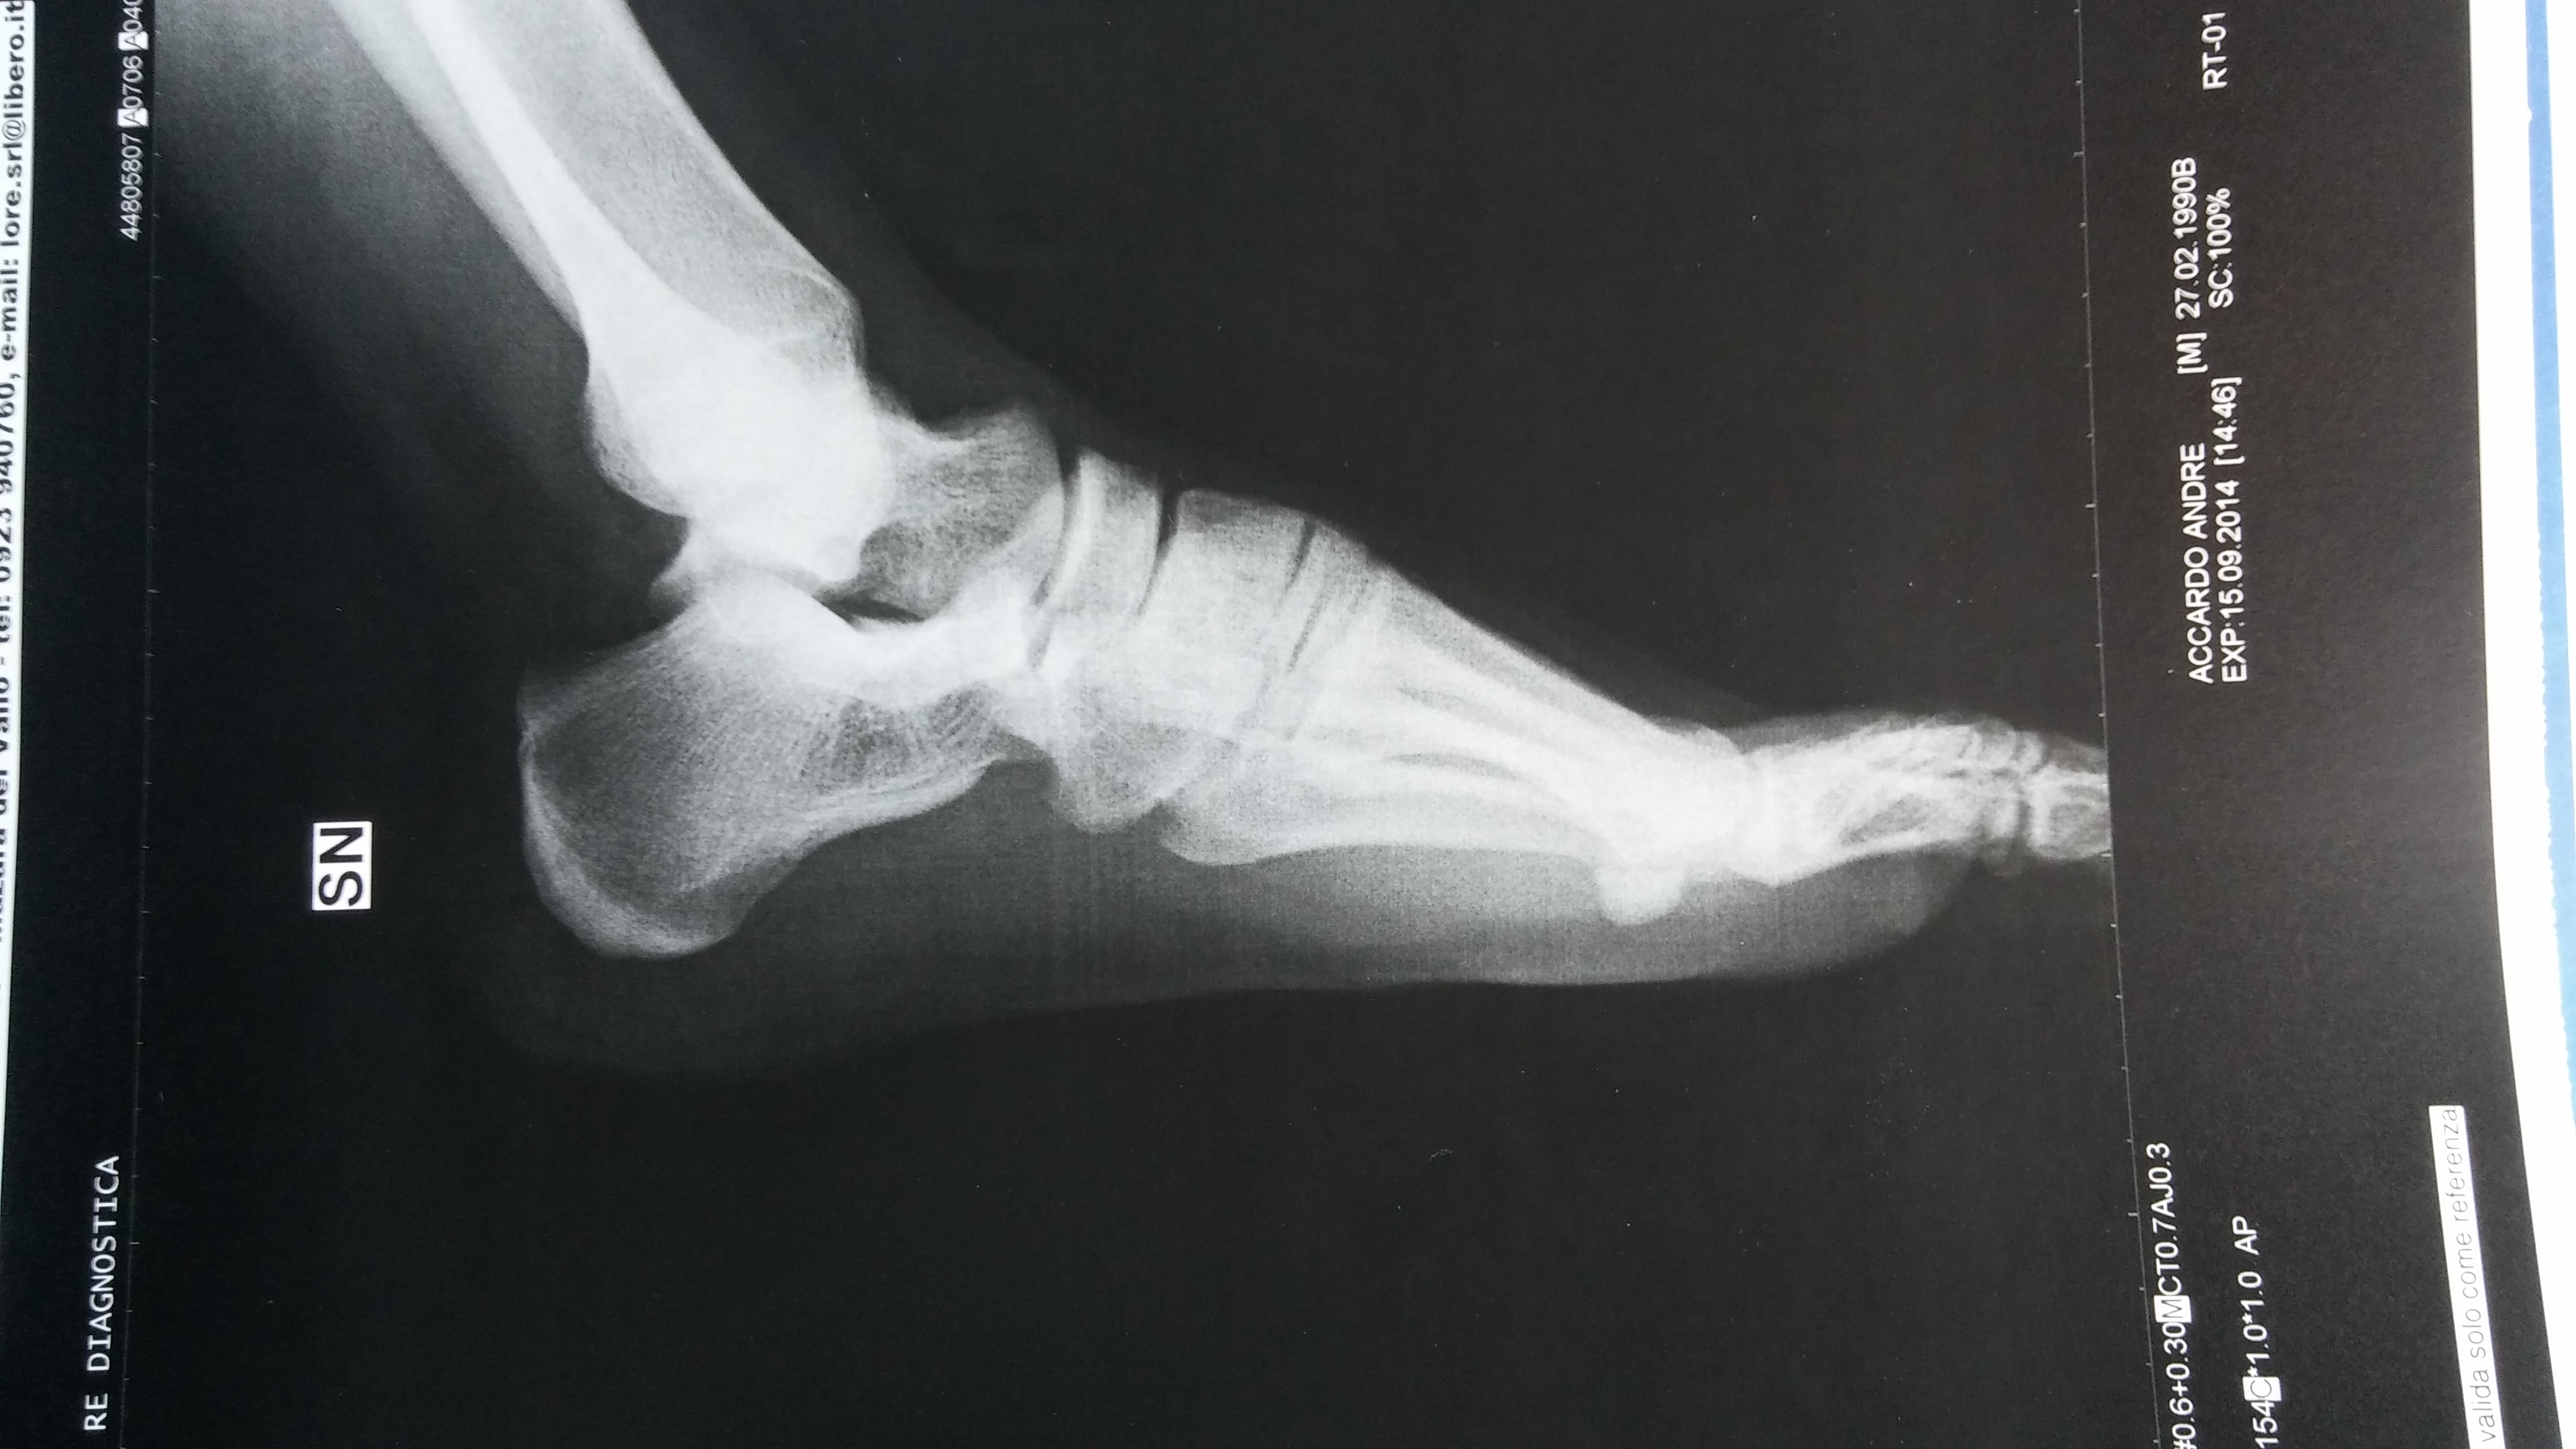

Quindi il fisiatra mi ha consigliato radiografia per sospetto sperone calcaneare. Risultato Nessuno Sperone.

in allegato sia Radiografia che Ecografia.

Commento file: diagnosi Rx

Commento file: Rx